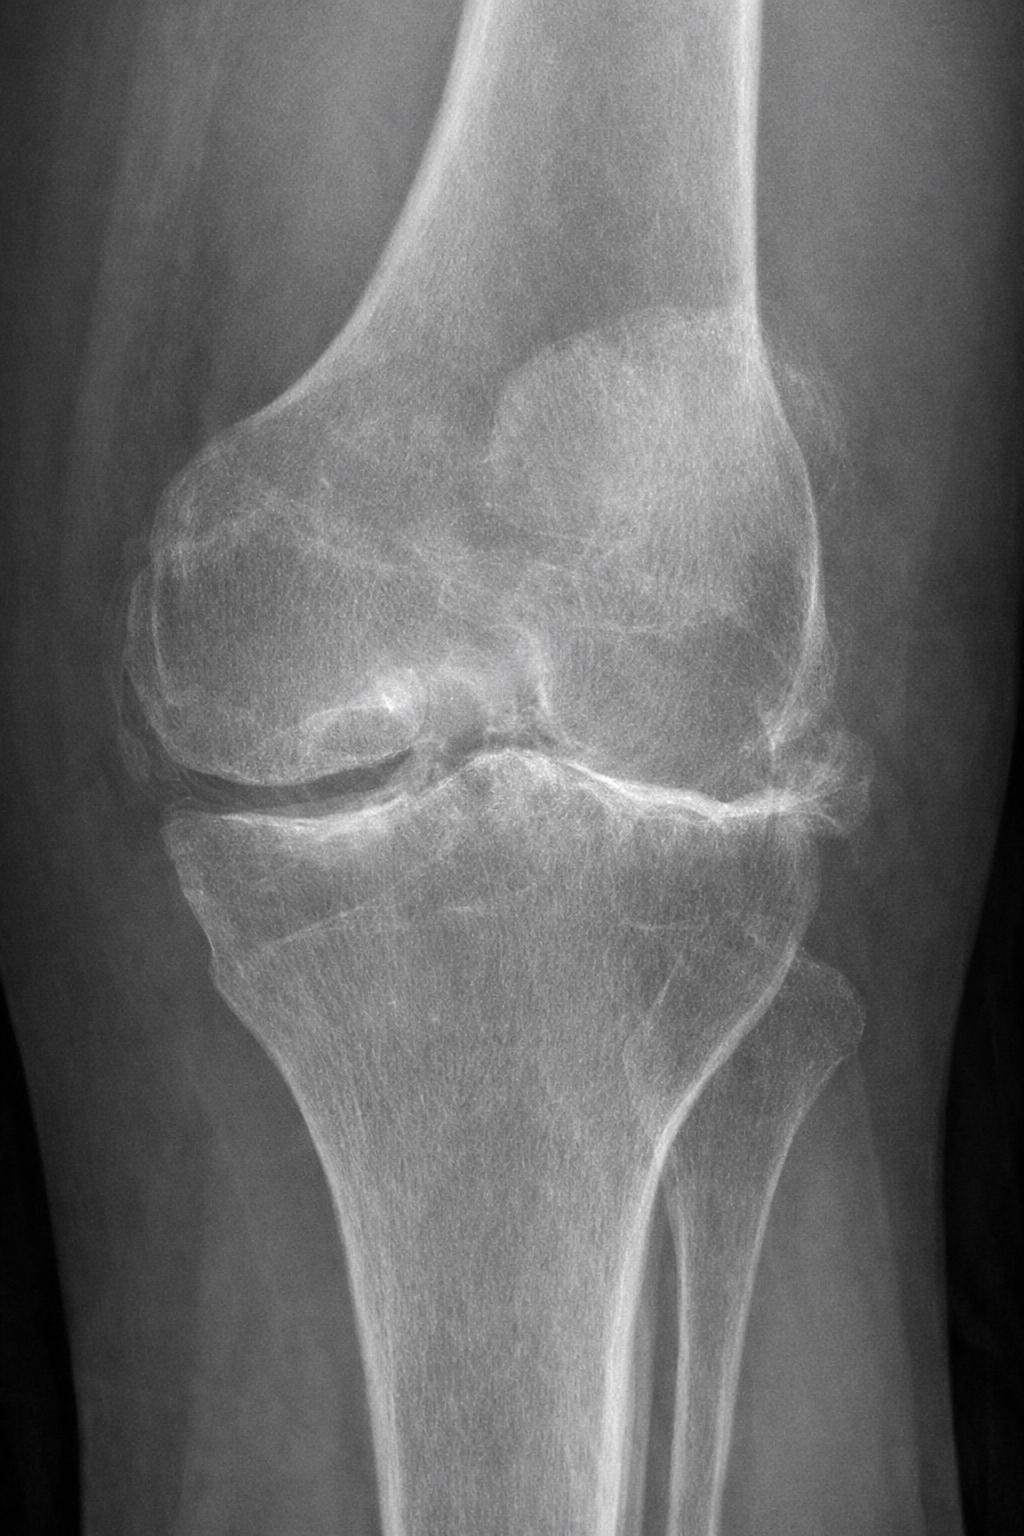

OSTEOARTHRITIS (OA) OF THE KNEE:

• Wear and tear type arthritis of the knee that damages cartilage, resulting in loss of normal function of the knee as bone starts wearing on bone

• Prevelance increases from age 60 to 70, with up to 40% of people affected by age 70